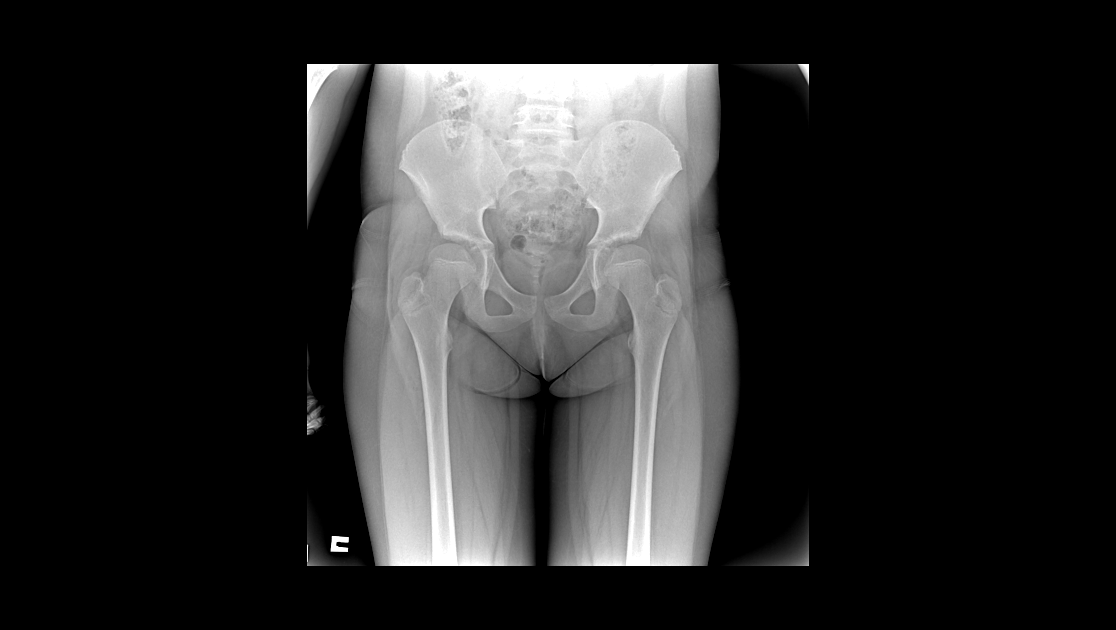

У меня дочь на скалодроме у пала с высоты метров 7.Поставили диагноз компрессионные переломы грудного и поясничного отдела позвоночника.А сейчас судебно-медицинский эксперт говорит,что у неё нет компрессионных переломов,а есть грыжи ранее приобретённые. Дочька до этого занималась только плаваньем.

Есть снимки.

Судя по представленным данным судебно-медицинский диагноз и, соответственно, степень тяжести вреда здоровью определены верно. Достоверных объективных признаков компрессионных переломов позвонков не установлено.

Клиновидная деформация тел позвонков и грыжи Шморля однозначно не свидетельствуют о костно-травматической патологии позвонков.

При необходимости проконсультируйте ВСЕ снимки позвоночника у опытного рентгенолога (лучше - при личном общении, т.к. при передаче через интернет может заметно уменьшаться детализация снимков). При наличии реально существующих оснований (оптимально - письменно выраженное мнение рентгенологов о достоверных признаках "свежих" переломов позвонков) - ходатайствуйте о назначении повторной суд-мед.экспертизы с включением в состав экспертной комиссии высококвалифицированных рентгенологов, детских травматологов-ортопедов, неврологов.

Смотрели 2 рентгенолога не зависимых друг от друга,ставят компрессионный перелом,лечащие врачи и рентгенолог больницы и рентгенолог травматологии и врач травматолог-ортопед ставят компрессионный перелом,все в один голос!